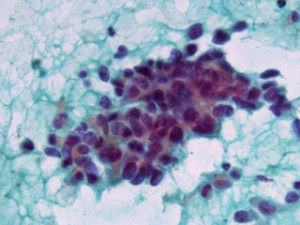

Tumore: alcuni nutrienti favoriscono la resistenza al trattamento

Il tumore può sfruttare il glucosio e un altro nutriente, l’acetato, per resistere alle terapie mirate rivolte a molecole cellulari…